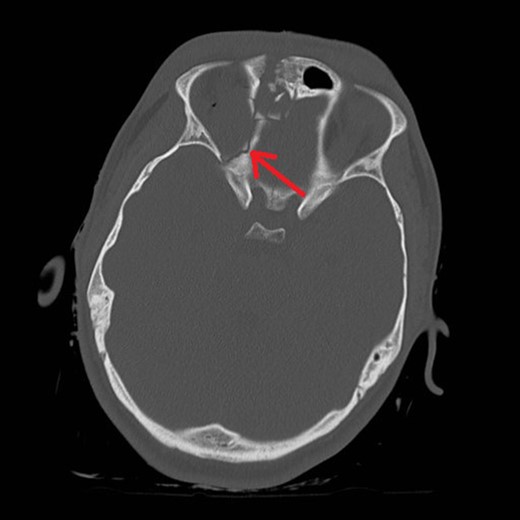

Mr AB is a 16-year-old male multi-trauma patient secondary to a high speed motor vehicle accident. His injuries included a frontal open comminuted depressed skull fracture with a fragment displaced and abutting the superior sagittal sinus (Fig. 1). The fracture line involved the right medial orbital wall extending through the ethmoid air cells and roof of the right sphenoid sinus (Fig. 2). Other cranial injuries included a fracture through the right side of the greater wing of the sphenoid bone, frontal intraparenchymal contusions and a traumatic subarachnoid/subdural haematoma. He had a laceration extending across the left side of his forehead to the medial canthus. His extracranial injuries included proptosis of his right eye, a closed unstable pelvic fracture with involvement of the left superior gluteal artery and a subcapsular liver haematoma.